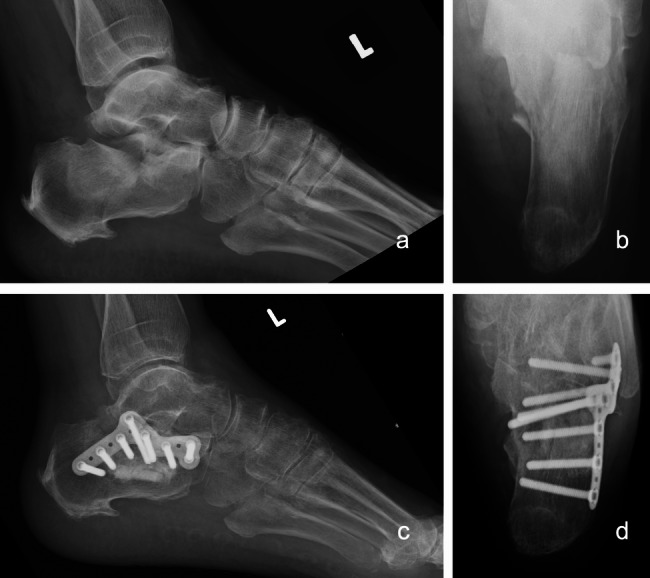

Methods: A total of 38 patients and 40 feet with DIACFs from 2015 to 2020 were retrospectively reviewed with a minimum of 3 years of follow-up. Patients were divided into two groups based on fixation method: minimally invasive locking plate fixation (MIP group) versus screw fixation (SW group) (17 vs 23, respectively). The clinical outcomes were evaluated by the Visual Analogue Scale (VAS), Maryland Foot Score (MFS), Olerud-Molander (OM) ankle score, American Orthopaedic Foot and Ankle Society (AOFAS) hindfoot score, and occurrence of complications. Radiological outcomes were assessed by radiographs for multiple parameters, including calcaneal height, length, width, and Böhler's angle.

Results: The patients were followed up for an average of 63.37 months. There was no significant difference in the final VAS score, MFS, OM score, AOFAS score, and the total incidence of complications between the two groups (P>0.05). Regarding the radiological outcome, there was also no significant difference in the reduction loss of calcaneal height, length, width, and Böhler's angle (P>0.05) after a one-year follow-up period. However, the rate of implant removal in the MIP group was significantly greater than that in the SW group (P< 0.05).

Conclusions: Minimally invasive locking plate fixation versus screw fixation of DIACFs via sinus tarsi approach may yield comparable radiological and functional outcomes. The screw fixation group suggested a shorter surgical time and lower implant removal rate. Both surgical methods are viable options for DIACFs. However, further large-scale prospective studies are warranted to confirm these results.